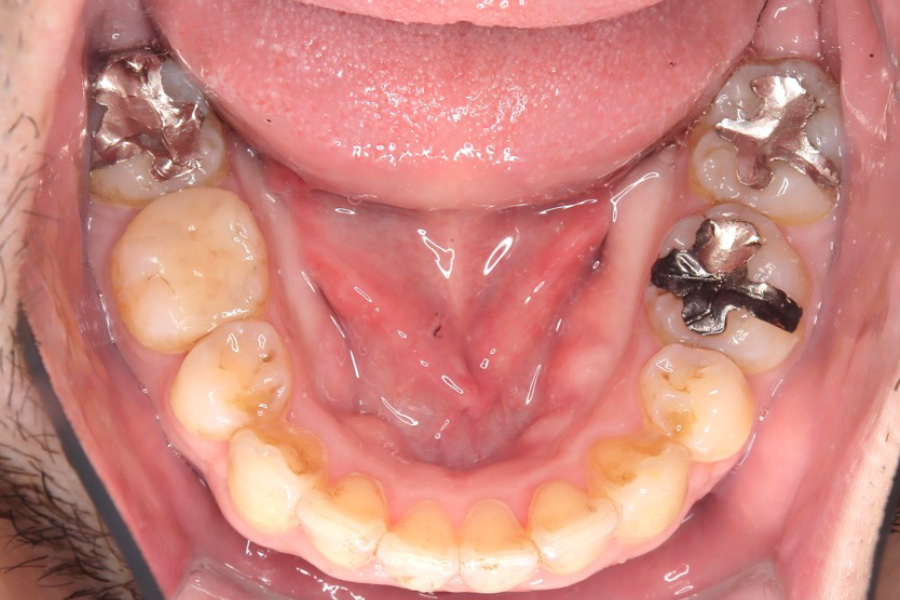

【30代男性】

下の歯のガタつきを

インビザライン矯正で治療したケース

治療前

治療後

| 主訴 | 下の歯のガタつきが気になる |

| 期間 | 1年 |

| 費用 | 220,000円〜660,000円 (デンタルローン 3,100〜6,600円/月) |

| 治療内容 | インビザライン矯正 小臼歯抜歯 |

| 治療に伴うリスク | 矯正終了後は、リテーナーを指示通りに使用し、歯の後戻りを防ぐ必要があります。 |